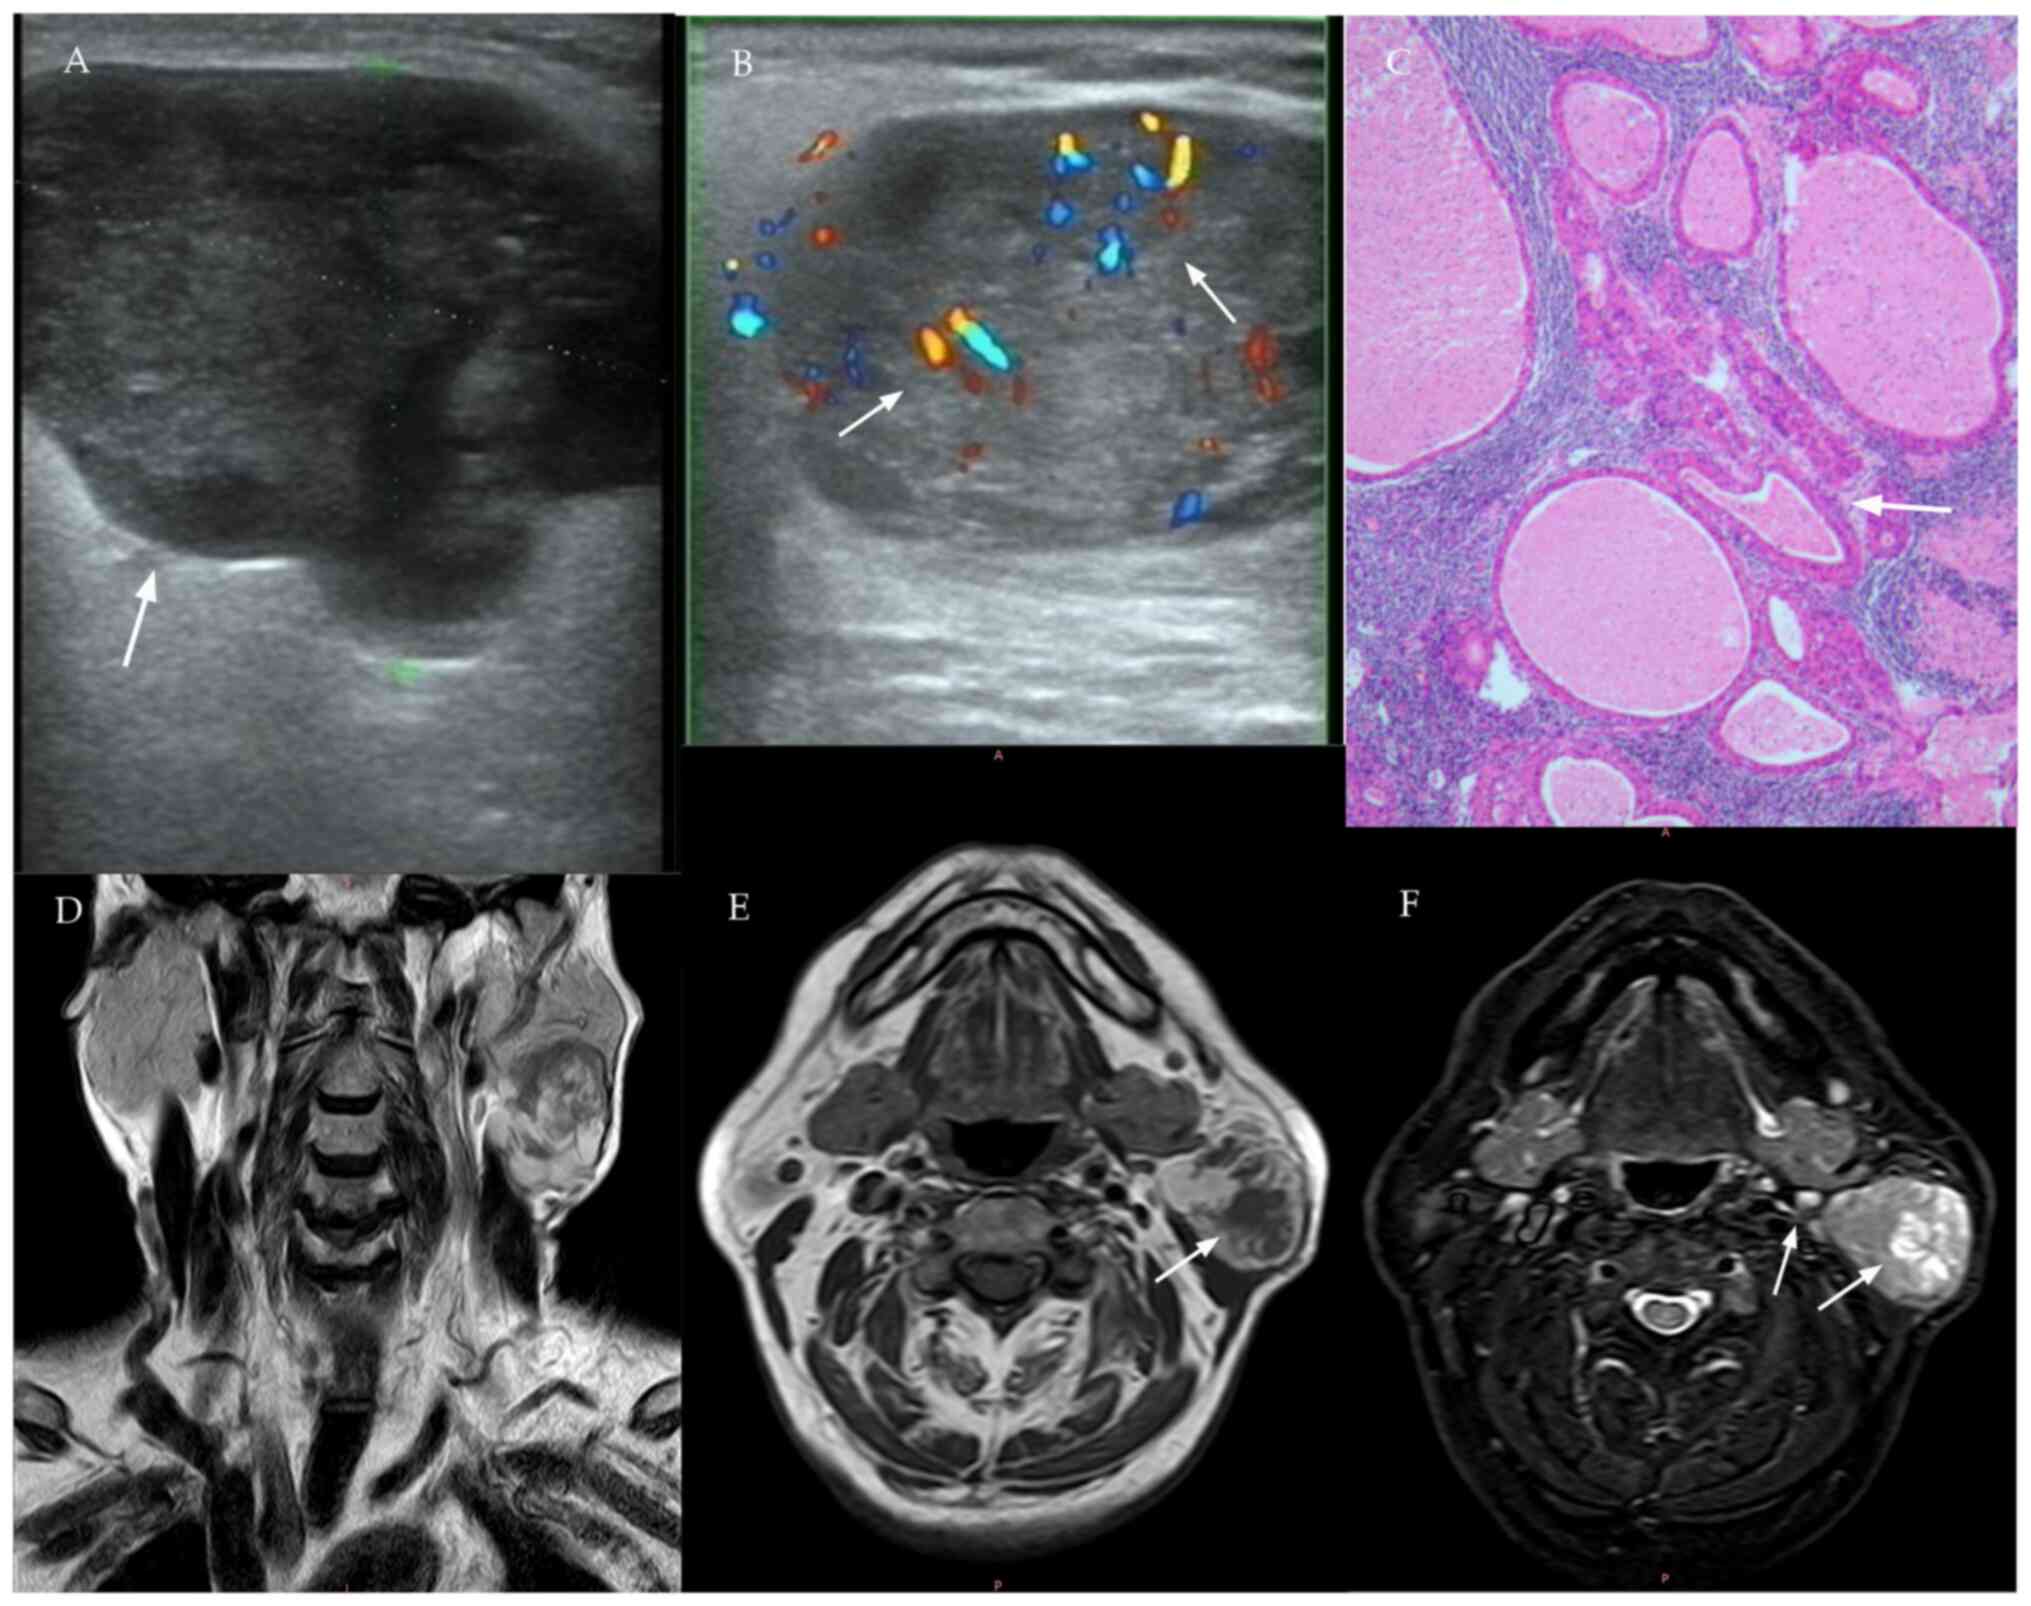

Features of malignant tumor

(mucoepidermoid carcinoma) on US, MRI and histopathology. (A) US

shows an irregularly contoured mass with indistinct margins, marked

hypoechogenicity and pronounced heterogeneity. (B) Color Doppler

demonstrates moderate intralesional vascularity (arrow). (C)

Histopathology (H&E stain): Tumor stroma with dense lymphoid

infiltration, multiple cystic formations and variably distributed

epithelial nests showing squamous differentiation, intermediate

cells and goblet cell metaplasia. (D) Coronal T2-weighted MRI:

Irregular peripheral margins with heterogeneous signal intensity

and nodular components (arrows). (E) Axial T1-weighted MRI:

Homogeneous hypointensity (relative to parotid gland parenchyma).

(F) Short Tau Inversion Recovery sequence: Diffuse signal

heterogeneity with enlarged cervical lymph nodes (arrows). US,

ultrasound.

Figure 2

Features of malignant tumor (mucoepidermoid carcinoma) on US, MRI and histopathology. (A) US shows an irregularly contoured mass with indistinct margins, marked hypoechogenicity and pronounced heterogeneity. (B) Color Doppler demonstrates moderate intralesional vascularity (arrow). (C) Histopathology (H&E stain): Tumor stroma with dense lymphoid infiltration, multiple cystic formations and variably distributed epithelial nests showing squamous differentiation, intermediate cells and goblet cell metaplasia. (D) Coronal T2-weighted MRI: Irregular peripheral margins with heterogeneous signal intensity and nodular components (arrows). (E) Axial T1-weighted MRI: Homogeneous hypointensity (relative to parotid gland parenchyma). (F) Short Tau Inversion Recovery sequence: Diffuse signal heterogeneity with enlarged cervical lymph nodes (arrows). US, ultrasound.